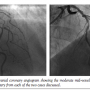

We report two cases where despite a good aortic pressure trace at the start of the procedure, there is damping of the dynamic pressure trace during hyperemia, secondary to axial migration of the guide into the left main stem (LMS). This is especially an issue with Q/CLS/EBU/Voda-shaped guiding catheters, which have more of a tendency to deeply intubate

the LMS than Judkins-shaped guides. Both of the cases involved intermediate-severity left anterior descending (LAD) arterial stenoses in middle-aged, average-sized males presenting with stable angina (Figure 1). A 6 Fr CLS 3.5 guiding catheter and a standard 0.014˝ intracoronary pressure wire (Volcano PrimeWire) via the right radial approach were used. A total of 500 µg of intracoronary nitrates were administered beforehand and hyperemia was achieved with 48 µg intracoronary injections of adenosine, as is standard for our institution.